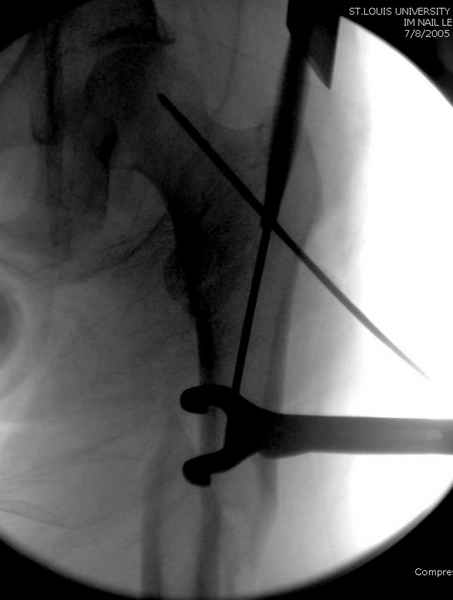

Как раз недавно у меня был примерный случай: больному 36 лет, поступил ночью, травма в результате мотоциклетной аварии, кроме чрезвертельного и спирального перелома левого бедра имеется переломы костей предплечья с этой же стороны. Скелетное вытяжение, а на следующий день больной про оперирован на ортопедическом столе с дистракцией. Чтобы не расколоть чрезвертельный перелом провели временную спицу ближе к переднему кортексу, из малого разреза костодержатель для репозиции, а фиксацию провели антиградным штифтом. Этапы операции на снимках.